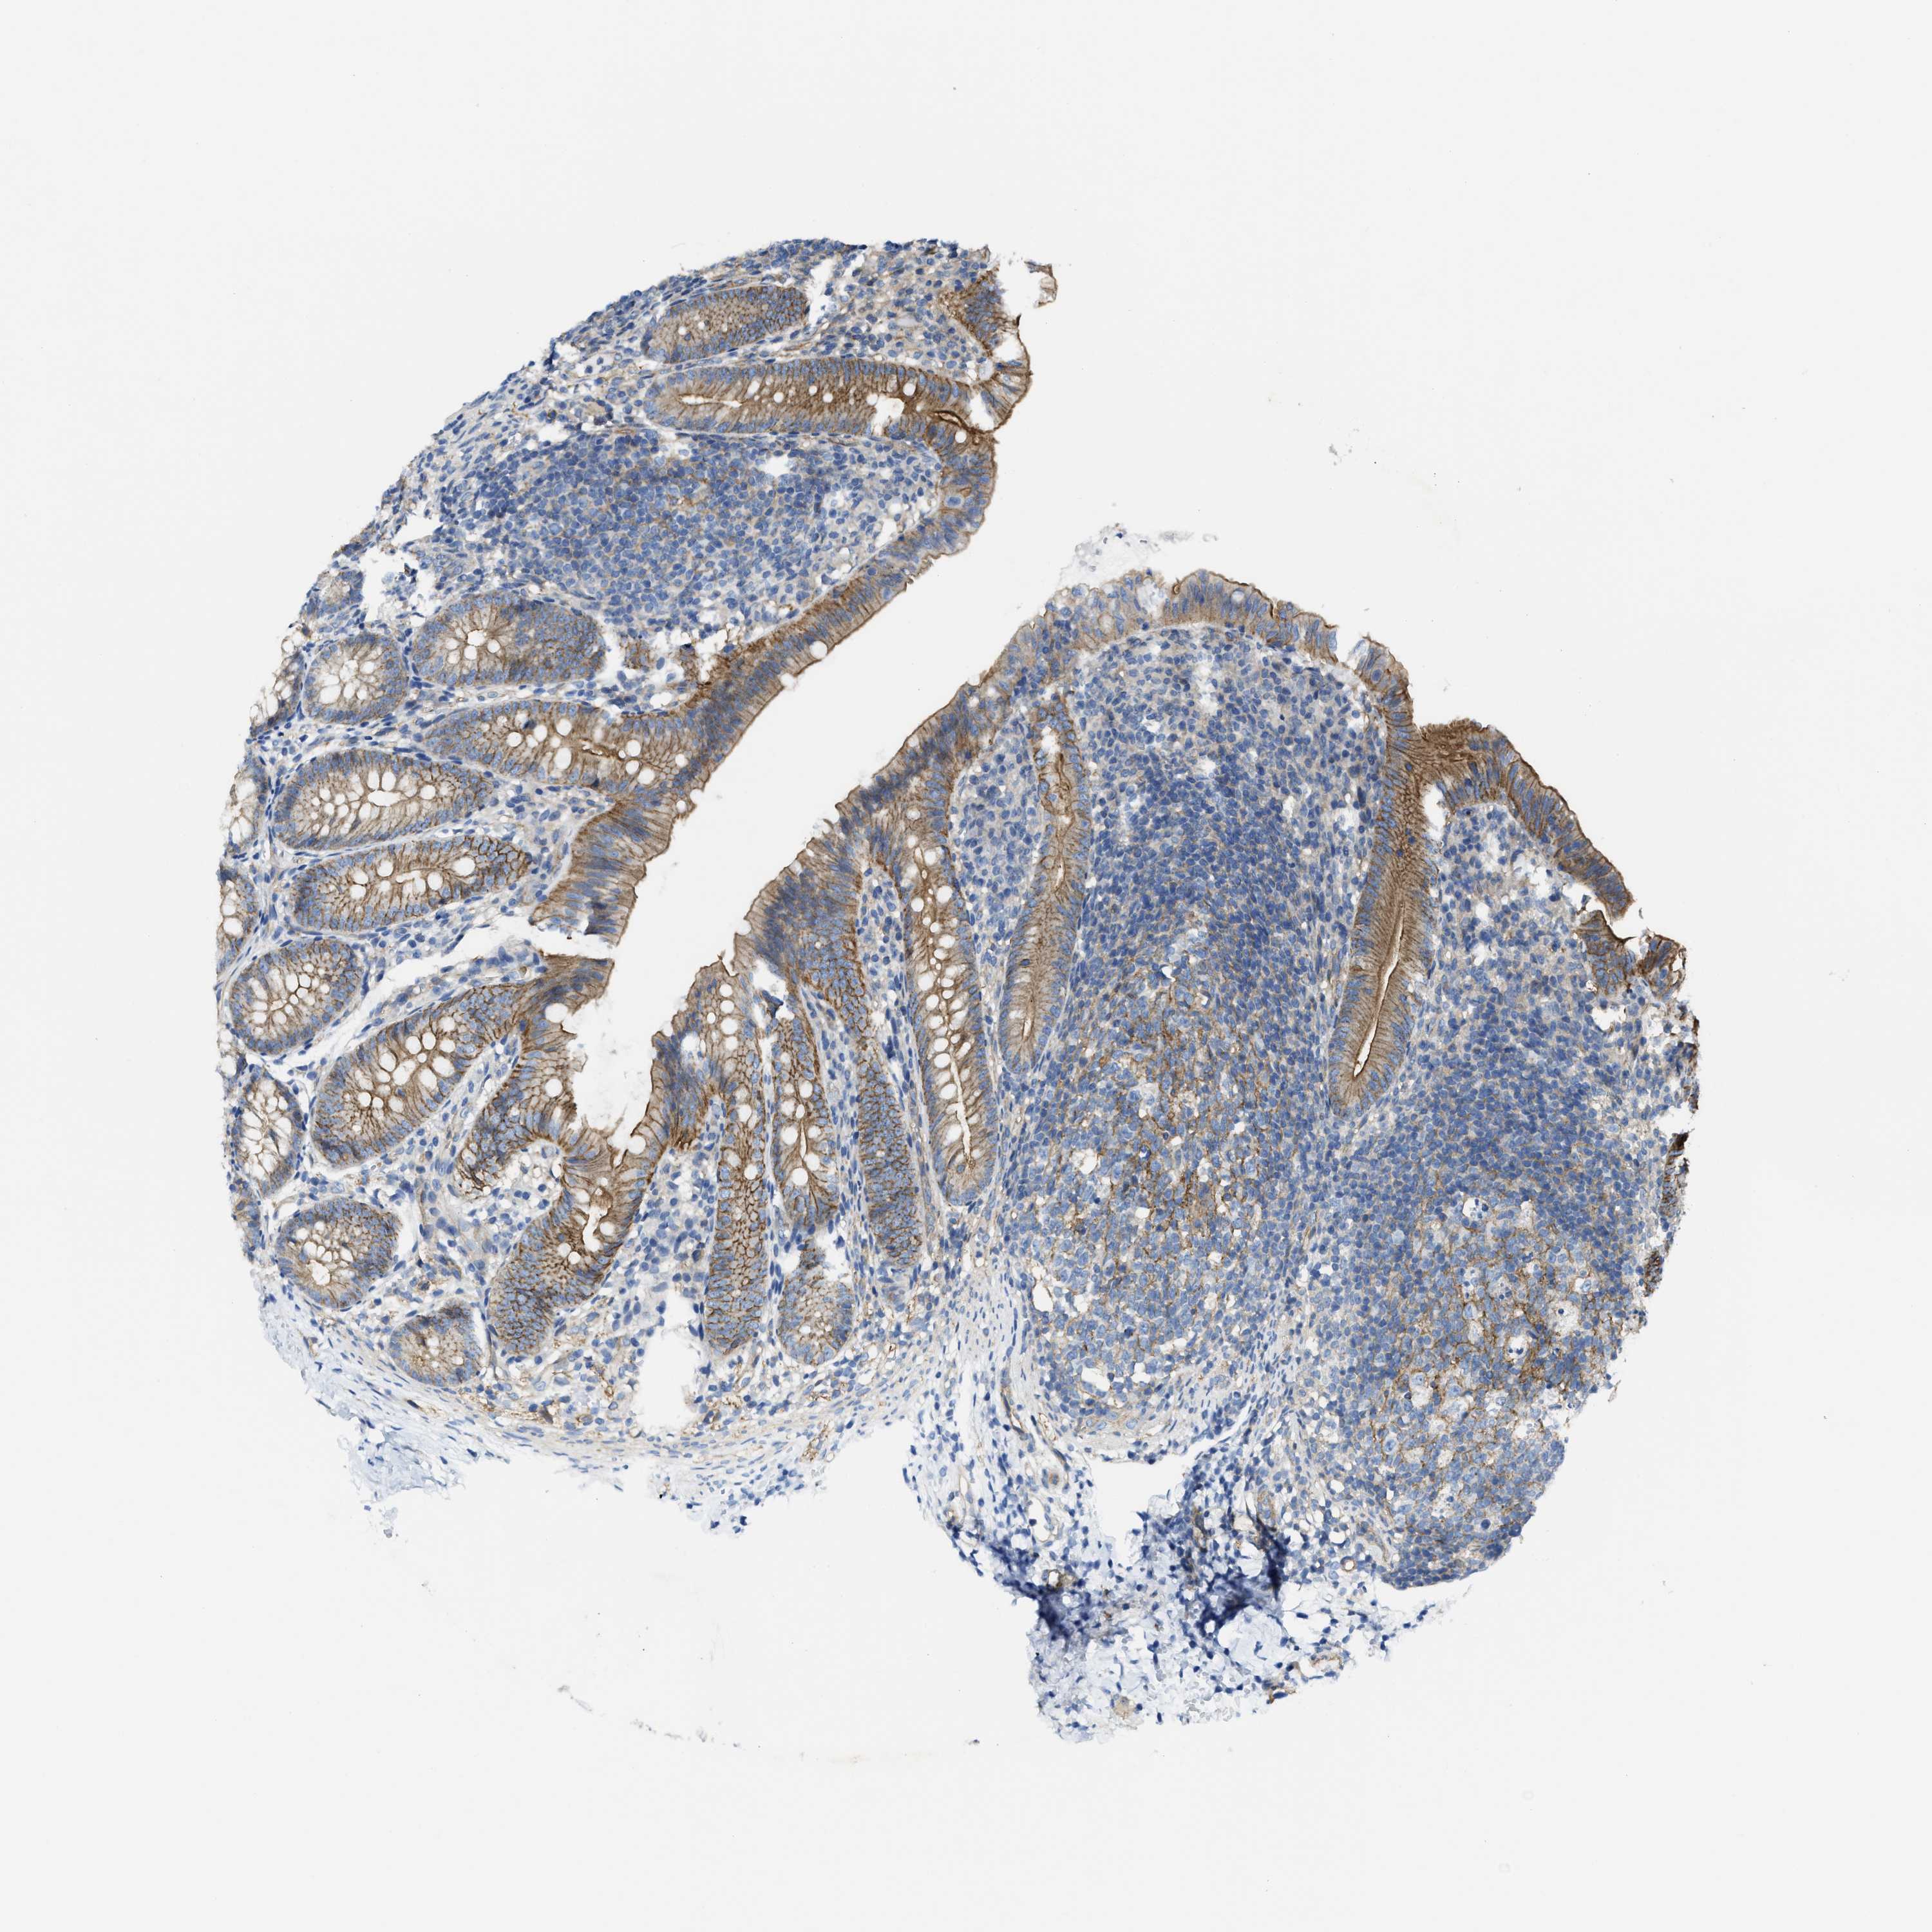

MMRN2